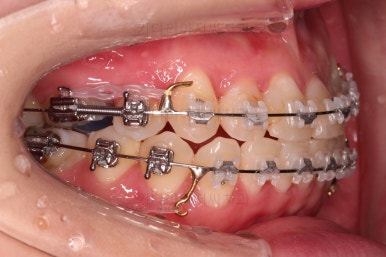

옆모습 중간중간 체크해 주고요.

이번 환자분은 옆라인이 애초에 매우 좋으셨기 때문에 입매를 바꾸지 않아야해서 오히려 더 세심한 치료가 필요한 환자분이셨습니다.

공간을 줄여나가고 순차적으로 충치치료도 마무리 해갑니다.

교합이라던가 부족한 부분을 좀 더 마무리하고요.